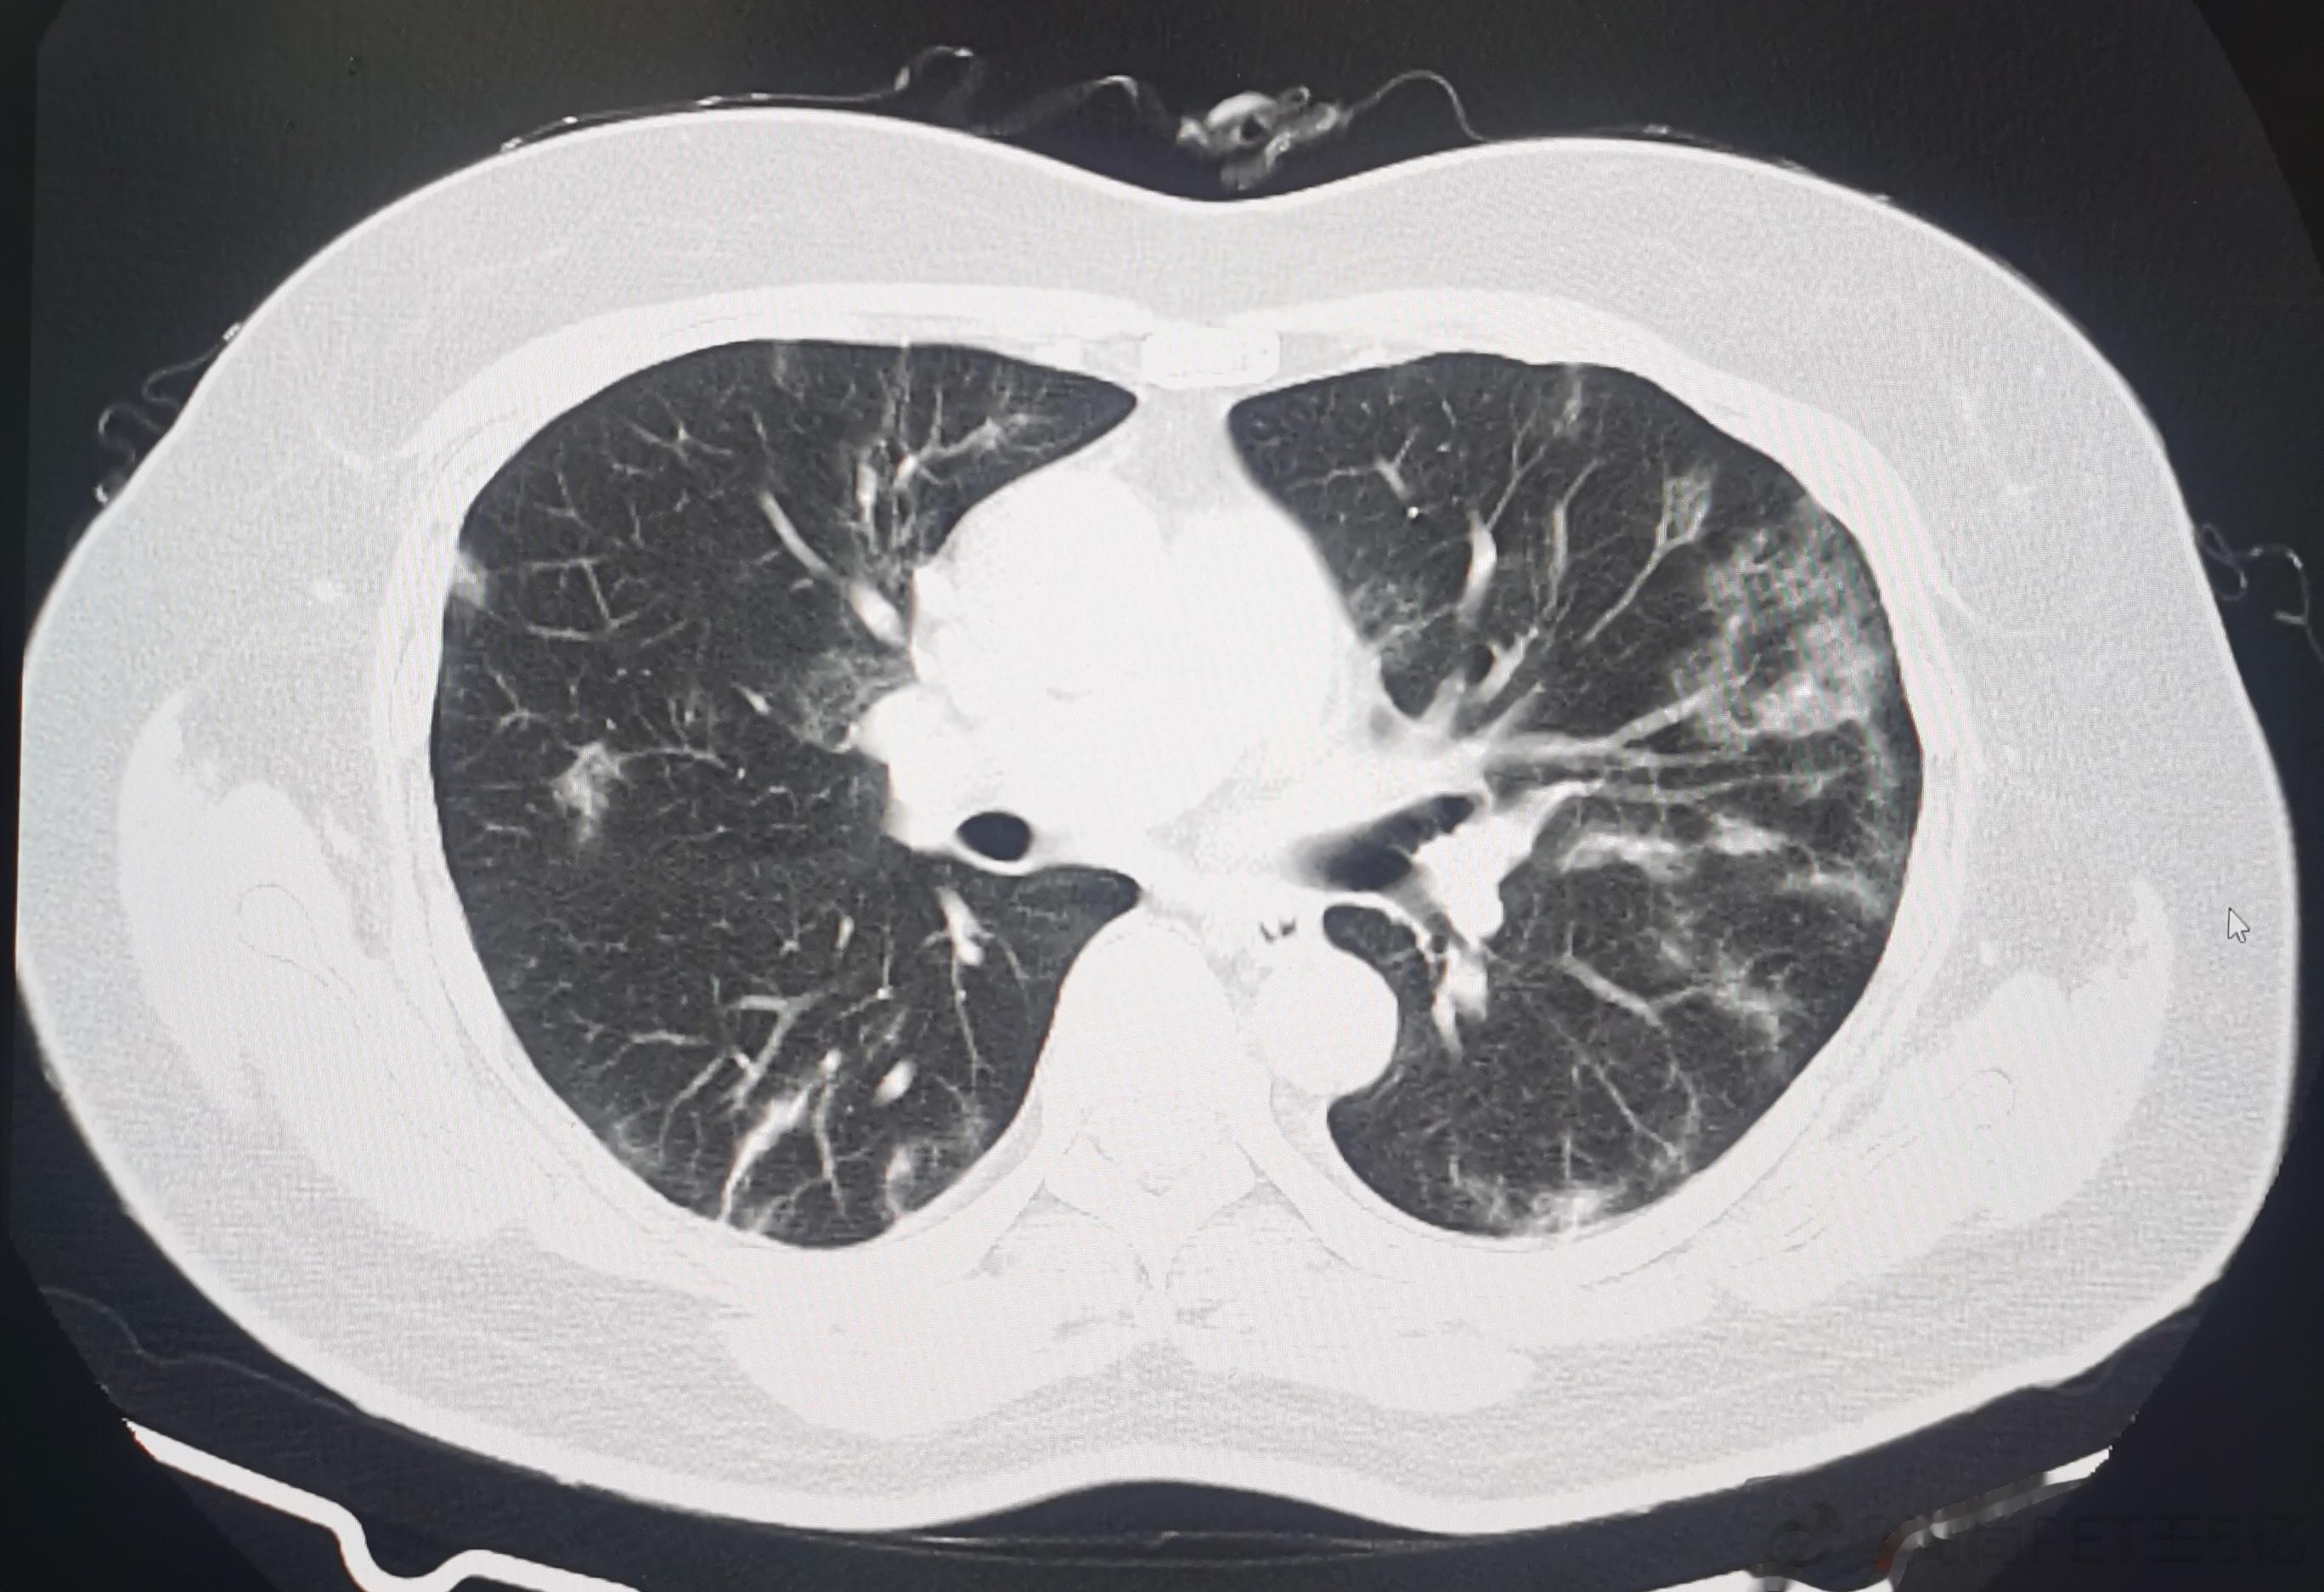

今日我们高尚影像中心新冠肺炎筛查病人是108例,其中28例有轻度新冠肺炎影像表现,检出率接近26%,最最小14岁(下面第一排CT图像),最大年龄是87岁(下面第二排CT图像),大部分人的年龄超过60例。由此可以看出,新冠病毒肺炎可能会累及各个年龄段,但主要还是60岁以上老年人群。如果新冠感染超过2周咳嗽症状还不减轻者,最好做一个胸部CT判断有无新冠病毒肺炎,这对于决策治疗方案及预测治疗效果都很关键。#老年人感染新冠后小心肺炎##感染新冠都要做CT吗#

今日我们高尚影像中心新冠肺炎筛查病人是108例,其中28例有轻度新冠肺炎影像表现,检出率接近26%,最最小14岁(下面第一排CT图像),最大年龄是87岁(下面第二排CT图像),大部分人的年龄超过60例。由此可以看出,新冠病毒肺炎可能会累及各个年龄段,但主要还是60岁以上老年人群。如果新冠感染超过2周咳嗽症状还不减轻者,最好做一个胸部CT判断有无新冠病毒肺炎,这对于决策治疗方案及预测治疗效果都很关键。#老年人感染新冠后小心肺炎##感染新冠都要做CT吗#